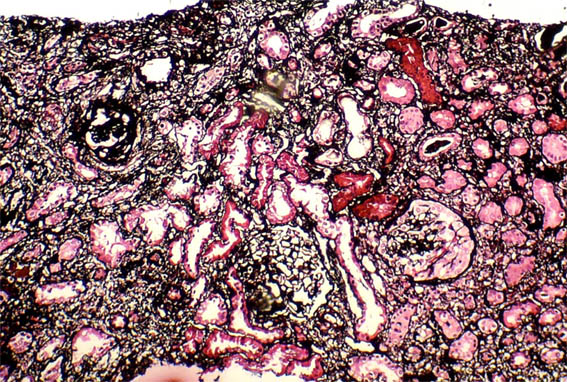

Figure 2. Masson's trichrome stain, X100.

Figure 6. Methenamine-silver stain, X100.